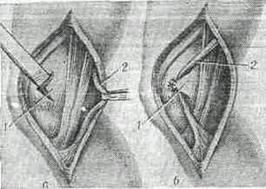

Оперативное вмешательство заключается в создании новой крестообразной связки вместо разорванной. Существует несколько методик, технически мало отличающихся друг от друга. Различие состоит только в материале и ткани, из которых создается связка. Для восстановления связки используют широкую фасцию бедра, часть собственной связки надколенника сухожилие двуглавой мышцы бедра, некоторые травматологи применяют мениск. В последние годы для этих целей довольно широко используют ленты синтетических тканей (капрон, лавсан), а также консервированные аллогенные сухожилия.

Операция восстановления передней крестообразной связки заключается в широком вскрытии сустава, просверливании каналов во внутреннем мыщелке большеберцовой кости и наружном мыщелке бедра, через которые проводят ленту из ткани и закрепляют ее концы на боковых поверхностях мыщелков.